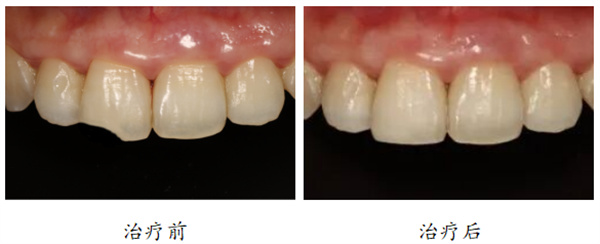

1. 牙体缺损

“我小时候把牙磕掉了一点儿,能做贴面吗?”

“牙齿缺了角角、表面坑坑洼洼,或者是长了浅浅的虫牙,这样的都是可以通过贴面来修复的。还有一些朋友的牙齿缺了一点,尝试用树脂补过,但是过不了好久就容易掉,也可以选择贴面来恢复美观。”